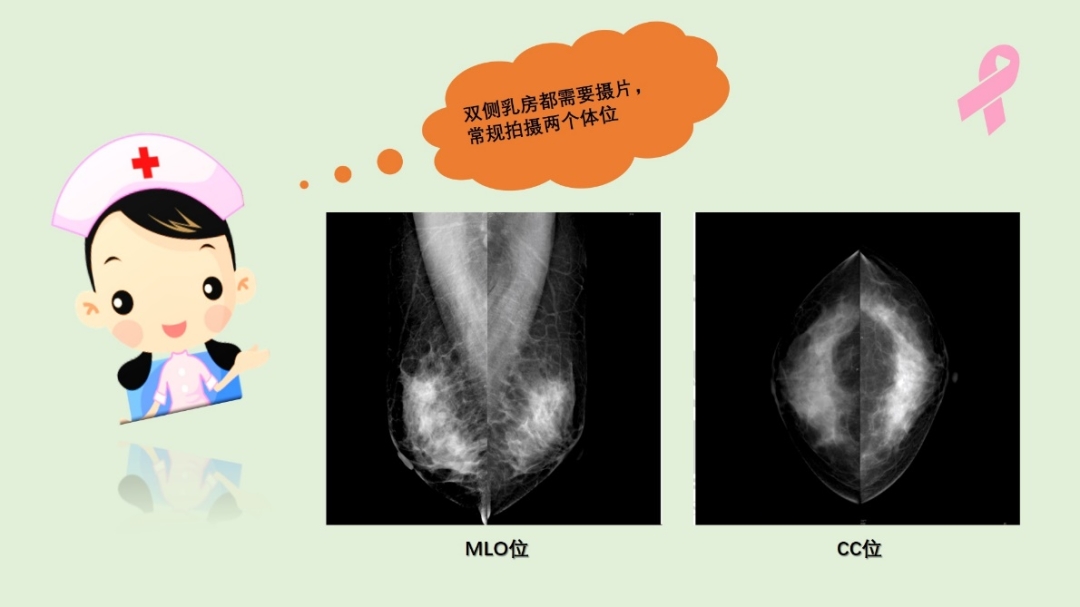

一般情况下,乳腺X线检查时双侧乳房都需要拍片,常规进行两个体位拍摄。将乳腺从上至下压迫,拍摄头足位(CC位);从内上向外下压迫,拍摄斜位(MLO位),这样多角度的拍摄可以让病变无处遁形。